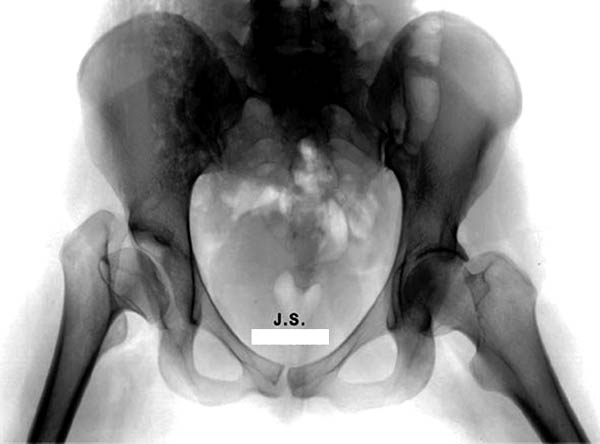

Представленный случай имеет схожесть...., и последний снимок после 2 х лет.

Возможность сохранить сустав, на мой взгляд, существует только гипотетически. Я за эндопротезирование с применением керамико-керамической (как вариант - металл-металл) пары трения. Важный момент - восстановление нормального оффсета, для чего необходимо тщательное планирование с оценкой рентгенограмм противоположного сустава.